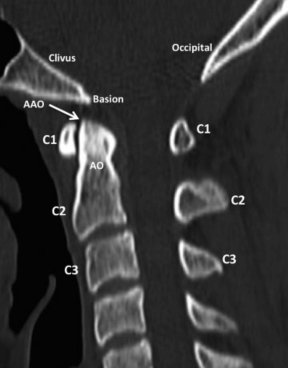

Está formada por la AAO y ambas AAA, o sea un total de 3 articulaciones integradas funcionalmente. La AAO se produce entre la AO de C2 y una carilla articular pequeña situada en la cara posterior del arco anterior de C1. El compartimiento articular se completa por detrás por el ligamento transverso (LT), queluego revisaremos (►Fig. 5). Por su geometría, permite sobre todo movimientos de rotación, y la AO por su anatomía y función es el verdadero pívot del raquis sub-occipital. Las AAA, de localización lateral, son equivalentes a las articulaciones inter-articulares del resto del raquis (o facetarias) y son fundamentales ya que acompañan los movimientos de flexo- extensión y rotación que se producen en el resto de las articulaciones (►Fig. 6).

TCMD, reconstrucción sagital, ventana ósea. En la vista lateral se visualiza correctamente otra articulación de la UCC, una de las más importantes, la AAO, entre el arco anterior de C1 y la AO de C2. Abreviaciones: AAO, articulación atlanto-odontoidea; AO, apófisis odontoidea; C1, 1ª vértebra cervical; C2, 2ª vértebra cervical; C3, 3ª vértebra cervical.

TCMD, reconstrucción sagital, ventana ósea. En este corte, lateral a la línea media, se identifican las articulaciones que forman parte de la UCC: AOA y AAA. Abreviaciones: C1, 1ª vértebra cervical; C2, 2ª vértebra cervical; C3, 3ª vértebra cervical.